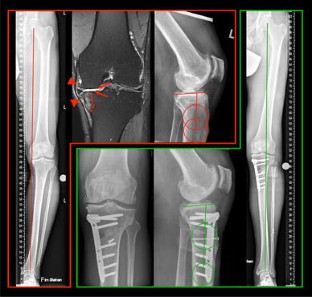

Fig. 1